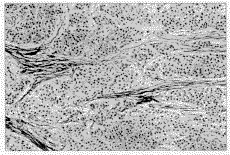

摘要 目的:探讨转化生长因子β1 (TGF-β1 )与原发性肝癌(PHC)发生发展的关系。方法:采用TGF-β1 多克隆抗体对29例人原发性肝癌组织进行ABC免疫组化标记,并做半定量分析。结果:在25例肝细胞肝癌中TGF-β1 表达显著高于正常肝组织及癌旁组织。高危转移组患者其表达明显高于低危转移组。TGF-β1 表达与肝细胞损伤血清学指标GPT及γ-GT有相关关系。结论:TGF-β1 与肝细胞肝癌的发生发展密切相关,TGF-β1 水平增高可增加肝细胞肝癌的转移危险性。

Abstract Objective : To study the relationship between TGF 1 and the genesis and development of primary hepatocarcinoma(PHC). Methods :ABC immunohistochemical staining with a polyclonal antibody against TGF- β1 was used in 29 cases of PHC. Results : In 25 cases of human hepatocellular carcinoma (HCC) ,the expression of TGF- β1 increased remarkably. The level of TGF-β1 was much higher in the patients with high risk of metastasis. The expression of TGF-β1 showed a significant correlation with serum GPT and Y- GT. Conclusion : TGF- β1 is closely related with the genesis and development of HCC. The higher level of TGF- β1 probably can increase the risk of tumor metastasis.